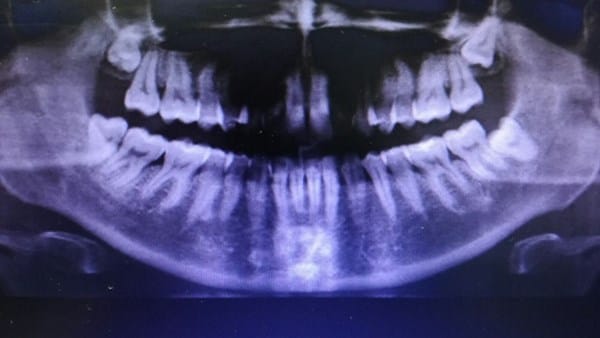

El cirujano maxilofacial opina que en un 80% la inflación del ganglio vienen de estos problemas dentales. Al extraer la cordal la zona tenía restos de anteriores inflamaciones. Él espera que, al extraer esta cordal, ya notemos que el ganglio vuelve a la normalidad, aunque ve que hay que extraer pronto la cordal superior derecha también y dice que en la radiografía se ve una pequeña fístula entre los molares de la parte superior derecha, que hay que revisar. Según el, el TAC no revelará mucho acerca del ganglio pues es tejido blando. Pero dice que me lo haga, por supuesto.

El día 20 de Septiembre tengo el TAC cervical. Y después la Biopsia. ¿Pueden darme una valoración del caso? La radiografía es de JUNIO, antes de extraerme la cordal inferior derecha.